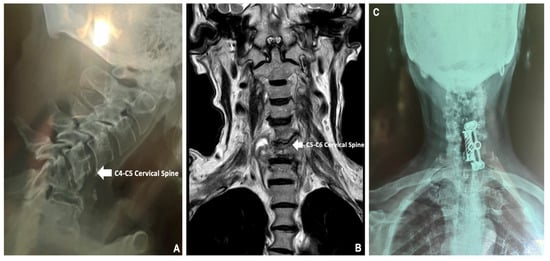

Following these findings, a GeneXpert MTB/RIF expectoration molecular biology test was performed and confirmed the presence of Mycobacterium tuberculosis complex without rifampicin resistance in the rpoβ gene, so treatment with pyrazinamide, ethambutol, rifampicin and isoniazid was started immediately. For evaluation of the generalized pain in the cervical area, which compromised mobility and caused gait disturbances, inflammatory biomarkers were requested, which revealed a C-reactive protein (CRP) concentration of 68.39 mg/L, Erythrocyte Sedimentation Rate (ESR) of 50 mm/H, and Uric Acid (UA) concentration of 12.2 mg/dL; in addition, an anteroposterior and lateral X-ray of the cervical spine was performed, where there was evidence of crushing of the vertebral body of C5 and C6 (Figure 3A), which was complemented with an MRI of the cervical spine in simple phase to T6, where a crush fracture of the C6 and C7 bodies was reported, with changes in the intensity of the intersomatic disc, in addition to an anterior paravertebral and retropharyngeal component, conditioned by narrow cervical canal C5–C6 and C6–C7, with bilateral C6 and C7 radiculopathy, associated with spondylitis (Figure 3B). Images were suggestive of granulomatous infectious etiology, for which treatment measures were reinforced with oral pyridoxine 50 mg daily, pregabalin 150 mg daily and etoricoxib 90 mg daily, with no adverse events observed during the treatment administration. Finally, an assessment was requested by surgery, in which it was decided to place an anterior fixation of the cervical spine with a threaded basket and an automatic titanium block to improve the patient’s prognosis (Figure 3C). During surgery, a bone sample was obtained from the C6 and C7 bodies, which was examined by histopathology, where the final diagnosis of Pott’s disease was made.

Figure 3. (A): Lateral X-ray of the cervical spine showing crushing of the C5 and C6 vertebral bodies. (B): Simple MRI up to T6, showing crushing of the C6 and C7 cervical bodies. (C): Anterior cervical spine fixation with threaded basket and automatic titanium locking.